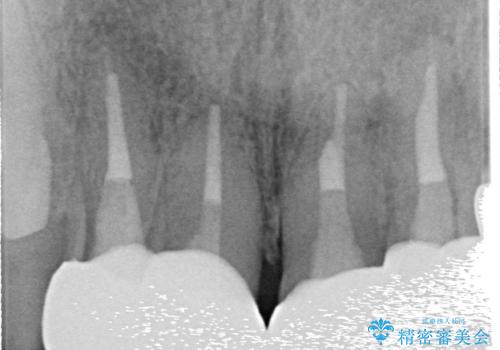

- 前歯の見た目が気になるといらっしゃった方の症例です。

再根管治療後、オールセラミッククラウンによる補綴を行いました。

右上2は歯茎のラインを整えるため歯周外科を行っております。